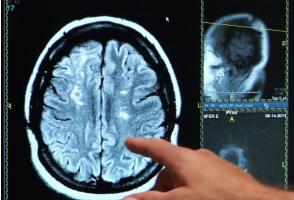

GROSSESSE : Ses complications annoncent un risque accru d'AVC précoce

Une histoire compliquée de la grossesse peut en effet annoncer un risque d’AVC précoce, avant même la ménopause, annonce cette étude menée par des médecins de l'Université Radboud de Nimègue, (Pays-Bas). L’étude, publiée dans la revue Neurology appelle, en cas d’antécédents de ces complications de grossesse, à une surveillance plus rigoureuse de la santé cardio et cérébrovasculaire.